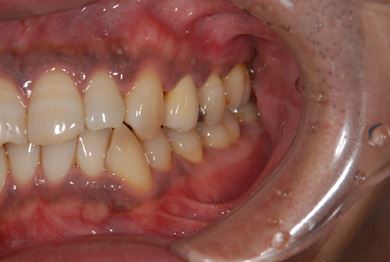

セラミック治療+歯肉歯槽骨整形術

| 性別/年齢 | 男性 / 45歳 | ||||||||||||||||||||||||||||||||

| 主訴 | 詰め物をしている歯が割れてしまったので、治療して欲しい。 | ||||||||||||||||||||||||||||||||

| 治療方針 | セラミック治療にて、審美的回復を行う。 | ||||||||||||||||||||||||||||||||

| 治療内容 | メタルボンドセラミッククラウン1本(メタルボンドセラミック用土台1本)、歯肉歯槽骨整形手術 | ||||||||||||||||||||||||||||||||

| 総治療費 | 157,185円 | ||||||||||||||||||||||||||||||||

| 治療期間 | 7ヶ月 |